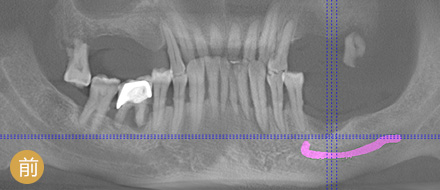

数字化精确导航种植

导航辅助种牙,创口小更舒服

• >避免盲种,成功率高

• >种牙精准,不伤神经

准确程度 依赖医生个人判断种植角度 外科导航系统定位,实时监控,避开血管神经

安全性 医生个人经验决定了种牙效果 神经、血管可见,导航全程定位,